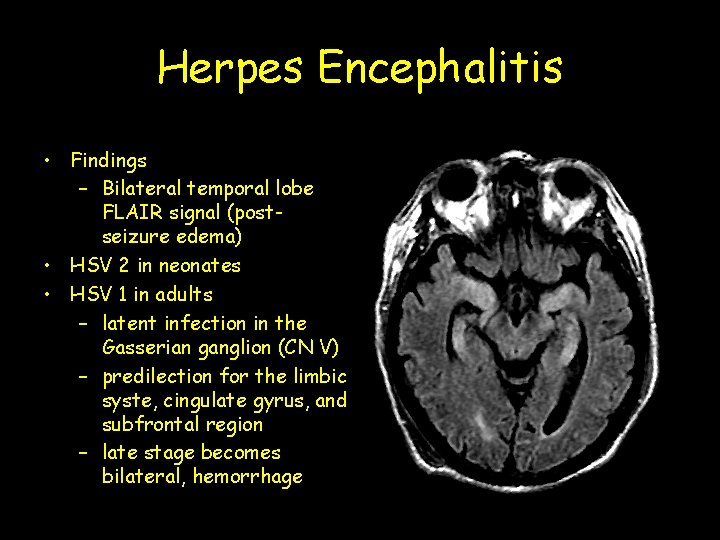

Herpes Encephalitis • Findings – Bilateral temporal lobe FLAIR signal (postseizure edema) • HSV 2 in neonates • HSV 1 in adults – latent infection in the Gasserian ganglion (CN V) – predilection for the limbic syste, cingulate gyrus, and subfrontal region – late stage becomes bilateral, hemorrhage